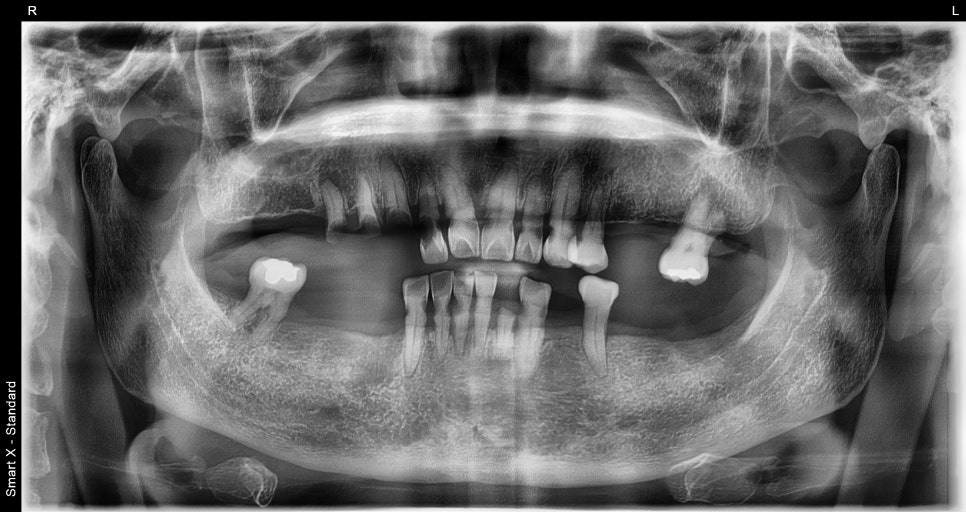

Seoulove Dental Hospital implants before

<Before surgery>

Condition at the Time of Visit

The patient had delayed dental care for more than 30 years,

and as a result, overall tooth wear, tooth loss, and gum inflammation

had developed together.

In particular, almost all molars were missing,

so chewing function had been lost,

and the remaining teeth were severely worn,

making it difficult to maintain the bite.

Food was repeatedly trapped between the gums,

causing recurring inflammation and odor,

and even everyday meals were very uncomfortable.